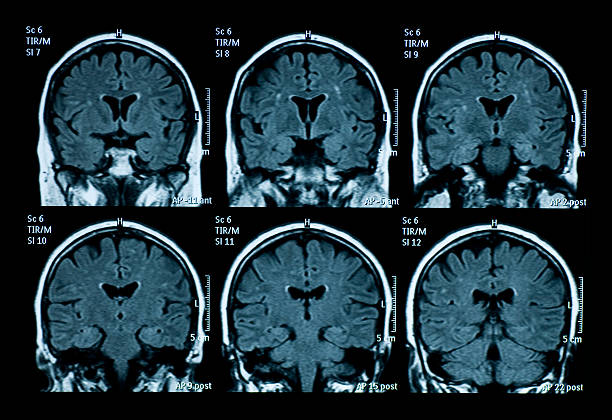

За туморот дознал откако доживеал напад во автомобил со колега, по што итно бил пренесен во болница. Прегледите откриле голем тумор со димензии 75 на 35 милиметри, сместен длабоко во централниот дел на мозокот. Бил подложен на операција, како и на радиотерапија и хемотерапија. Поради локацијата на туморот, по интервенцијата извесно време не можел ниту да оди ниту да зборува.